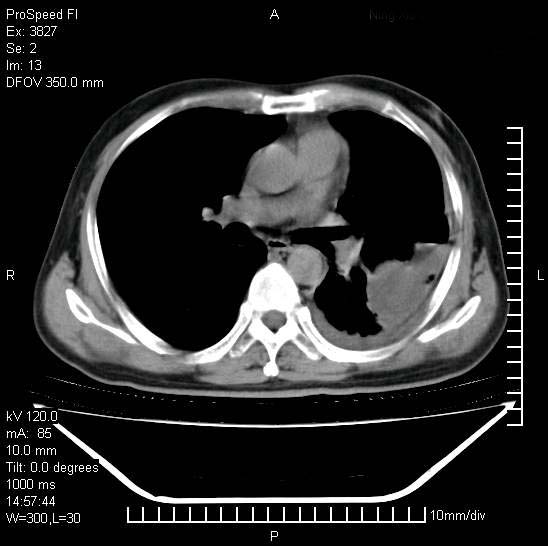

男性,一月前出现右侧肋区疼痛,较剧烈,干咳,无发热,自诉使用抗炎药后缓解,几天前又出现左侧剧烈疼痛,

发热,体温38。9,今天ct,考虑左侧包裹性脓胸,胸腔积液,右上中肺小斑片影,结核/炎症?胸水未见恶性细胞。

支持:脓胸!并双肺继发性肺结核!

脓胸!并双肺继发性肺结核!

左侧肺脓疡,化脓性胸膜炎(脓胸),不支持结核诊断,建议继续抗感染治疗

支持左侧肺脓肿并脓胸,肺内炎症,建议继续抗炎治疗后复查。

脓胸没问题,肺内还可见感染灶,感觉不像是结核性病变.